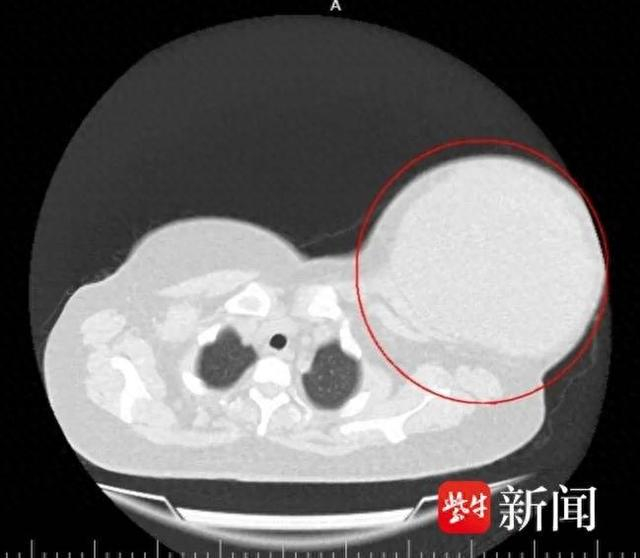

血常规提示患者伴有感染迹象,B超提示患侧乳房内有一个长达16厘米的囊性结节。进一步完善胸部CT及相关检查发现,肿瘤为囊实性,内部实性和囊性错综复杂,无数的分隔就像一个个蜂巢,实性组织的中间有很多充满液体的囊腔。